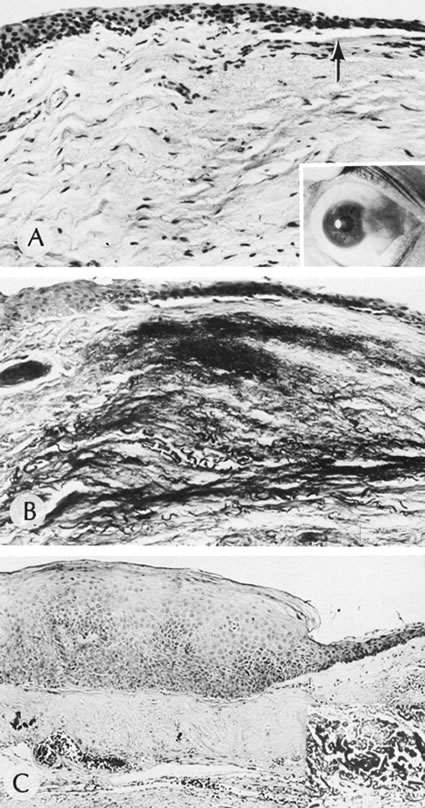

Syphilis is a venereal disease caused by the spirochete Treponema pallidum, which primarily affects the central nervous and cardiovascular systems. During the past decade, syphilis has again become more common. Often syphilis is found in patients who also have acquired immune deficiency syndrome (AIDS).101 The organism is highly infectious but of low virulence, resulting in long periods of latency and prolonged viability unless specifically treated. Many of the tissue effects of syphilis are due to host immune response, such as mononuclear cell infiltrates, proliferative vascular changes, and occasionally granuloma formation. The cornea often is not affected by acquired syphilis but is commonly affected by congenital syphilis (Fig. 12). Infection of the fetus occurs transplacentally after the fifth month of gestation. Diffuse fibrosis can compromise the function of any parenchymatous organ, including the lungs.

Fig. 12. Syphilis. A. Corneal ghost vessels as viewed by fundus reflex in a patient with congenital syphilis. B. Slit lamp appearance of interstitial keratitis. C. A blood vessel (arrow) present anterior to Descemet's membrane (d). D. Retrocorneal ridges of Descemet's membrane form refractile, branching straight lines. E. A multilayered strand extends from a thickened Descemet's membrane into the anterior chamber.(Courtesy of SEI Photoarchives.) (B Courtesy of Dr. W. C. Prayer; D and E from Waring GO, Font RL, Rodrigues MM et al: Alterations of Descemet's membrane in interstitial keratitis. Am J Ophthalmol 81:773, 1976.)

The cornea is particularly involved in a late-occurring form of congenital syphilis, which also causes periostitis, saber chins, saddle nose deformity, and tooth deformities (Hutchinson's teeth).102 Congenital syphilis presents between the ages of 5 and 10 years with an intense keratitis that may last for several months and may reduce visual acuity to counting fingers or seeing hand movements.103 Fortunately, usually a significant regression occurs with a parallel improvement of visual acuity, often in the range of 20/40 to 20/60. The acquired form of interstitial keratitis tends to be unilateral (it may even be sectorial) and tends to occur during the third or fourth decade of life as an expression of tertiary syphilis.

Histologically, the cornea shows edema and infiltration by lymphocytes and plasma cells. Vessels usually are seen in the deep portion of the cornea, just anterior to Descemet's membrane. Although the edema and inflammation of the corneal stroma resolves, the deep vessels persist in the form of ghost vessels. Often blood flow is minimal but persistent through the vessels, even though they appear empty. Chronic interstitial inflammation causes alterations of Descemet's membrane that are characteristic of congenital syphilis and include linear guttae with ridges and even nests of transparent basement membrane material, which may project into the anterior chamber.104,105